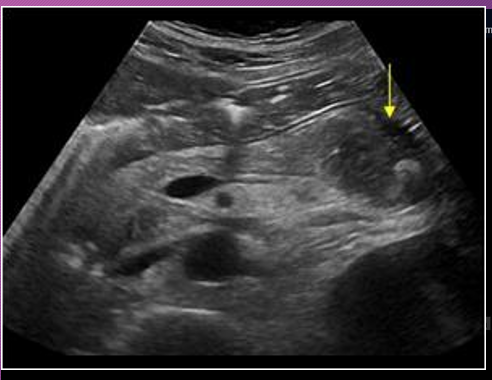

When swelling does occur in acute pancreatitis, the sonographic appearance of the gland becomes ______ to _____ and is less _____ than the ______

hypoechoic; anechoic; echogenic; liver

When _____ does occur in _____ pancreatitis, the sonographic appearance of the gland becomes hypoechoic to anechoic and is less echogenic than the liver

Swelling; acute

_____ pancreatitis will have somewhat ______ but ________ borders, sonographically.

Acute; indistinct; smooth

Acute pancreatitis will have somewhat indistinct but smooth ______, sonographically

Borders

Sonographically, pseudocysts appear as ____-_____ masses, _______ with increase through _______

well-defined; anechoic; transmission